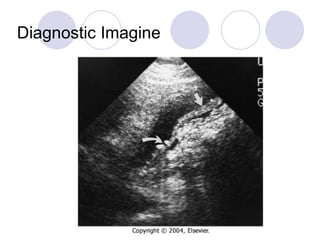

Diagnostic Imagine B-us Abdominal Plain film CT scan

Diagnostic Imagine B-usAbdominal Plain film CT scan